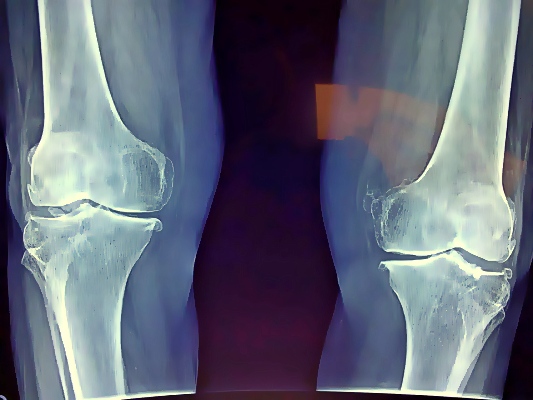

変形性膝関節症は、診察、X線(レントゲン)写真、MRIなどで診断します。

ただし、関節軟骨の摩耗が進んでいても痛みをあまり感じない患者さんがいたり、逆に摩耗があまり認められないのにもかかわらず強い痛みを感じる患者さんもいたりするなど、X線写真の画像と症状は必ずしも一致しません。

ひざは大腿骨(ふともも)と脛骨(すね)、膝蓋骨(ひざの皿)で構成されています。 これらの骨が靭帯、筋肉、関節のふくろなどの組織でおおわれ、関節としての機能を果たしています。

大腿骨・脛骨の接触部分は軟骨でおおわれ、その隙間にある半月板が、ひざへの負担を減らしています。